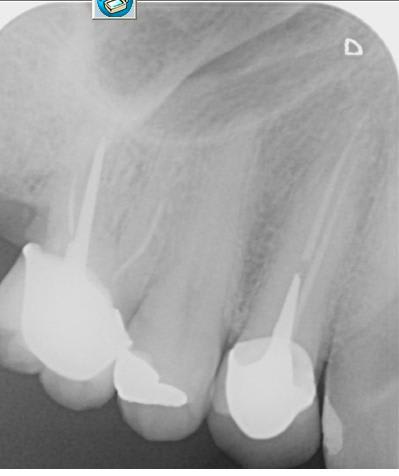

Voici la radio

Suspicion de fêlure ou fracture en effet. Sur la radio je ne vois rien de spécial.

J'ai juste une remarque sur la longueur de ton tenon qui me parait assez court (donc contraintes et risque de fracture augmenté). Comment travailles tu ? En tenon anatomique ?

Je dirais a vue de nez un bourrage avec la canine, si c'est le cas, refaire une couronne adaptée. Sinon effectivement le tenon est trop court.

A mon sens, si l'extrémité du tenon est en dessous du niveau osseux, de longueur équivalente à la couronne clinique (et que ça tient ^^) c'est suffisant. On voit régulièrement passer des dents avec des pieux énormes, dont le démontage représente un gros risque...

J'ai pourtant l'impression de voir une image longeant en mésial ce qui pourrait être la racine vestibulaire.

Il faudrait comparer avec la radio préop.

Je l'ai vu aussi cette image mais en fait en regardant tout autour je vois les trabeculations osseuses de la même densité de l'autre côté.

J'ai déduis que c'était l'os.

Mais peut être est ce +